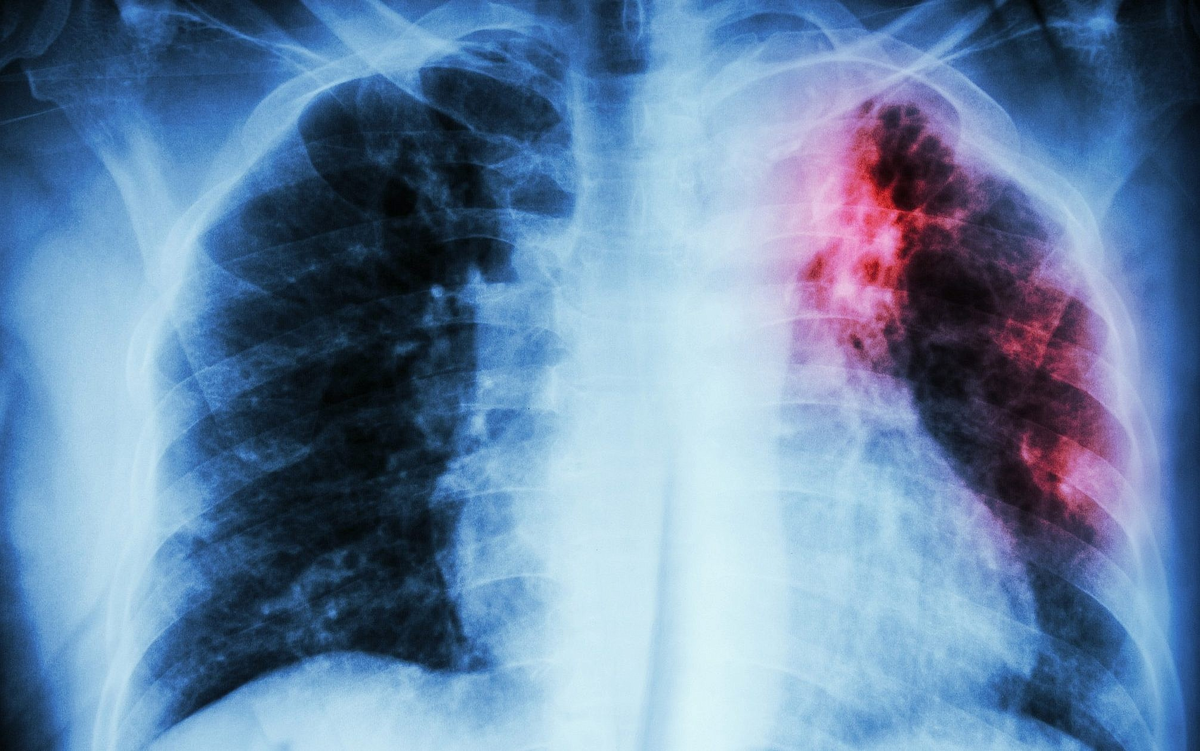

Легкие туберкулезного больного. Фото из открытого источника